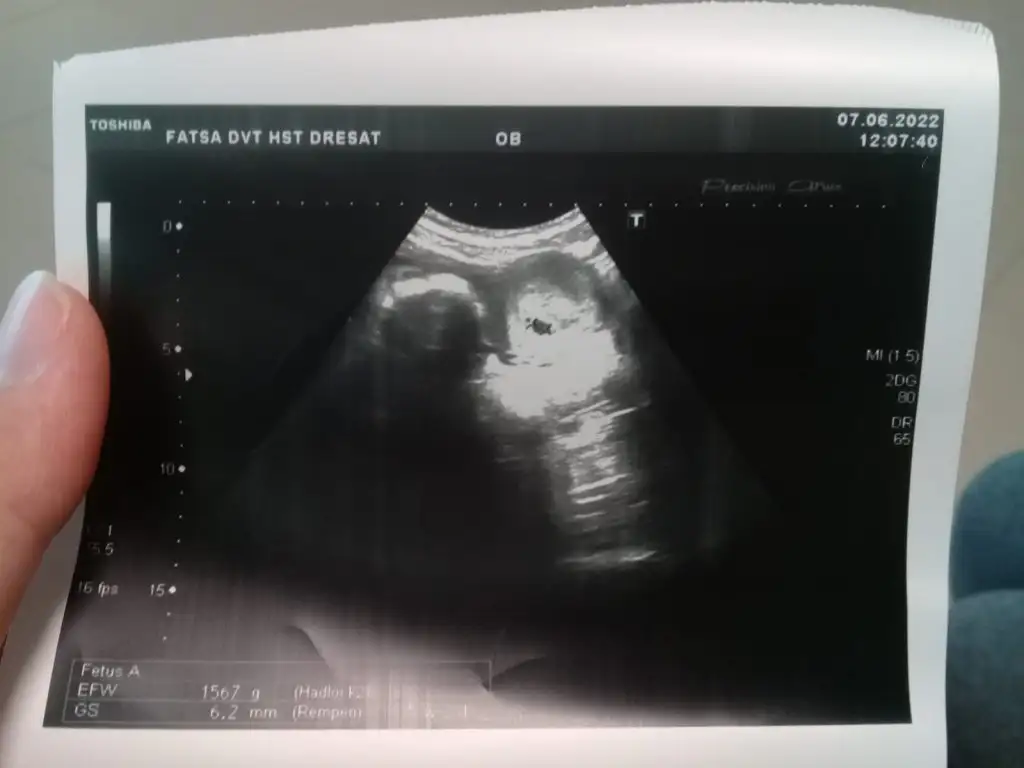

Bende 16 günde bir 10 gün regli oluyorum ama düzenli bir şekilde bende senin gibi düşünüyordum hamile kalsam bile hemen çıkmaz göremez diyordum adet günü test yaptım ve hemen ikinci çizgi çıktı ertesi gün kan verdim 54 çıktı köyde yaşadığım için daha gidemedim bu ayın sonunda hem keseye hem kalp atışına gidicem insaAllah nasipseHerkese merhabalar.. Ben 2 yıldır sürekli kendime benzer insanlar aradım ama hiç karşılaşamadım ne yazıkki. Şimdi ise hamileyim. Size biraz anlatmak ve sormak istiyorum. Benim regl döngüm 21-20 gün ile oluyordu ve sadece 2 hafta temiz kalıyordum bu durumda hamile dahi olsam öğrenebilmek için 10 gun gecmesi gerektigini dusunmustum.ne zaman test yapsam neredeyse her ay o silik hayalet cizgiyi görür sonra reglm başlardı. Bu ay yine günüm gecikti 2 gün sadece. Bende gittim kan testi verdim adetim henuz 2 gun geçerken beta hcg test sonucum 16.2 çıkmıştı. Tabi yine kimyasal gebelik ile düşük olduğunu sandm. Kan testinin ertesi gunu doktora gittigimde ertesi gün tekrar kan vermem gerektiğini 32 nin üzerine çıkarsa sağlıklı bir gebelik olacağını söyledi ultrasonda baktığında ise rahim duvarım kalınlaşmıştı bana eğer kanaman olmazsa 1 hafta sonra gel dedi. Doktordan ertesi gün kan verdim ve sonucum 64.4 çıkmıştı. Daha sonra 1 haftanın geçmesini beklerken cok siddetli agrilarim olmaya basladi ben düştugunden korkarak 1 gun ara ile tekrar kan verdim ve sonucum 152 çıktı(geçtiğimiz pazartesi günü). Bugün ise kontrolegittim ve miniğimin kesesini gördüm. 10 gün sonra kontrole gelmemi düşük haftalarında oldugum icin dikkatli olmam gerektiğini söyledi. Rabbim isteyen herkese bu duyguları yaşatsın inşallah❤ Ancak benim son adet tarihim 4 mayız başlaması gereken adet tarihimde 24 mayıstı bugun 15 gunum gecıyor. Hesaplamalarimda ve uygulamada 4+6 görünüyor ama ultrasonda 5+2 gözüktü kese boyutu ise 6.2mm acaba normalmi sizin kac haftada kaç mm idi??